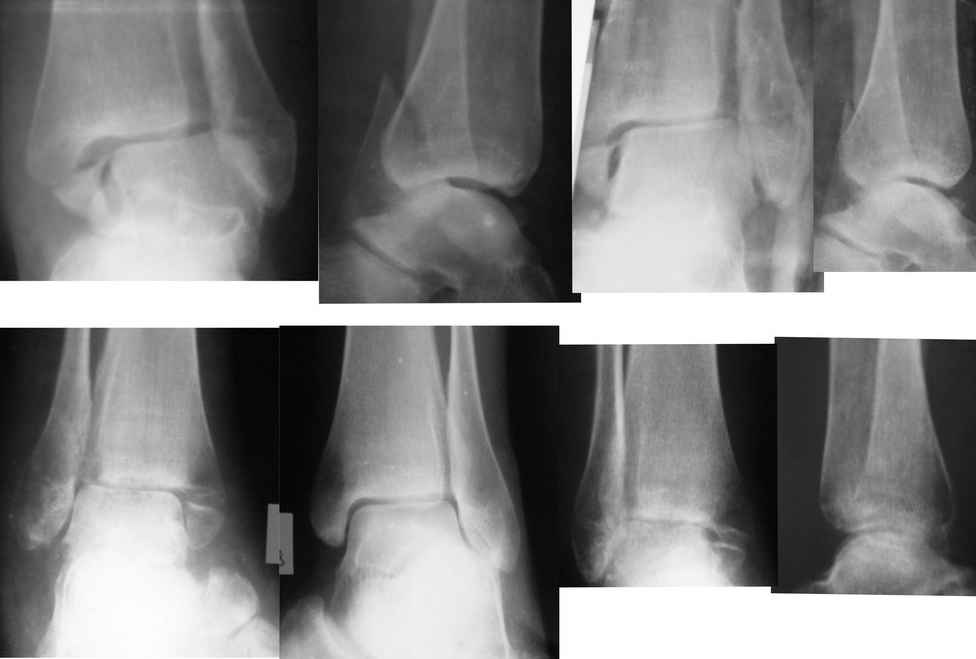

Gennady Tenison 07 Май 2010, 14:35

Евгений!. Вы сами ответили на вопрос. Оперировать безусловно, восстановить длину малоберцовой кости, позиционный винт и винты на внутреннюю лодыжку. Послеоперационное ведение как при свежем переломе, отсчет от дня операции, о потерянных двух месяцах придется больной забыть.

Re: Застарелый перелом лодыжек

Отправитель: Андрей Волна 07 Май 2010, 23:33

Да, абсолютно точно, Геннадий Вильгельмович. Разделяю Ваше мнение.

Единственное, в таких случаях более мощную пластину взамен классической 1/3 трубки предпочитаю выбирать. Или переходную метафизарную, что дороже. Или реконструктивную. Что бюджетнее.

Дедок Михаил 07 Май 2010, 23:11

Оперировать + ранее функциональное лечение.

Евгений 08 Май 2010, 00:24

Уважаемые коллеги, спасибо за помощь. Подберём более мощную пластину (есть в наличии малоконтактные). Фрагмент внутренней лодыжки небольшой, думаем синтезировать спицами и проволочным серкляжом.

Бережной Сергей 08 Май 2010, 00:57

Проволочный серкляж для внутреней лодыжки приведет к значительно большей травматичности вмешательства. Вполне можно обойтись 2 спицами или спицей и винтом. Все-таки основное внимание должно быть уделено наружной лодыжке. И, учитывая имеющийся регионарный остеопороз, лучше пусть будет более тонкая блокируемая пластина, чем мощная без возможности блокирования.

ANDREW 08 Май 2010, 02:33

А в чем вы видите большую травматичность при остеосинтезе по Веберу внутренней лодыжки? По-моему в предстевленном случае остеопоротические изменения могут привести к разлому лодыжки при остеосинтезе, а фиксация по Веберу даст не меньшую стабильность.

Бережной Сергей 08 Май 2010, 02:56

Большая травматичность при остеосинтезе по Веберу определяется необходимостью обнажения проксимальной части лодыжки для проведения проволоки. И неплохо было бы запланировать какую-нибудь стимуляцию остеогенеза на такое вмешательство. Дешевле и эффективнее взять с крыла подвздошной кости. Но это на вкус хирурга.

Бережной Сергей 08 Май 2010, 21:33

На рекомендованном Вами рисунке как раз отлично видна большая травматичность вмешательства в сравнении с остеосинтезом 2 спицами или спицей и винтом.

Александр А. 09 Май 2010, 00:38

Безусловно операция необходима. Думаю после востановления латерального компонента составляющей сустава, в сопоставлении медиальной лодыжки проблем не будет, а фиксация (каким способом лучше владеете), если уж хочется совсем малоинвазивно - канюлированные компрессирующие винты, а вобще думаю абсолютно не имеет значение разрез 3см или 3см3мм.

Вот только исходя из личного опыта считаю, что через два месяца после травмы позиционного винта на синдесмоз будет мало, не обойтись без старого доброго болта-стяжки, (по крайней мере у меня не получалось, это не свежая травма). Тем более послеоперационный период предполагается без внешней иммобилизации с ранним включением функции.